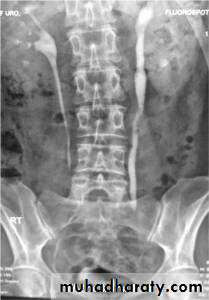

Intravenous Urography (IVU)

IVU